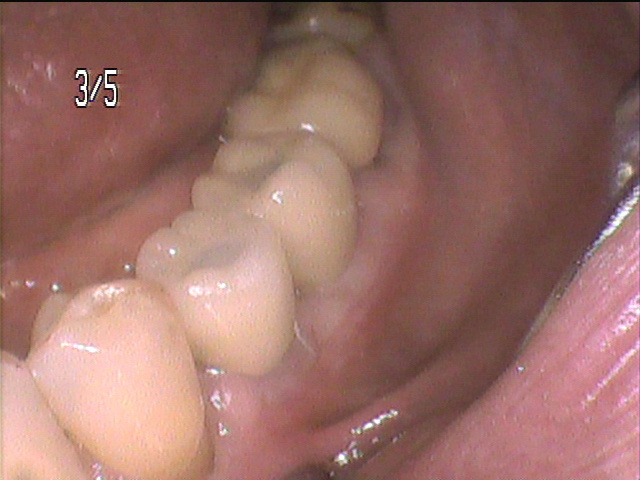

• インプラント治療事例にNO.61を掲載しました。

インプラント治療事例にNO.61を掲載しました。